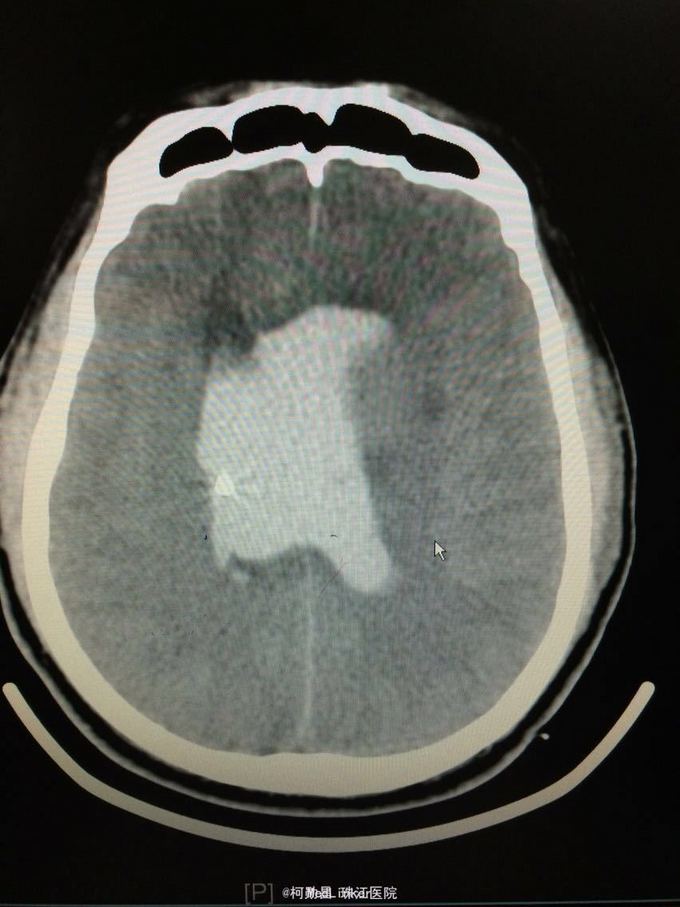

主诉:突发意识障碍4小时 病史:患者57岁男性,入院前一天晚上突发意识不清,伴呕吐胃内容物多次,无肢体抽搐等,随即由家人呼叫120送至我院,急诊行头颅CT提示左侧基底节区出血破入脑室。既往高血压病史10多年

查体:神志不清,双侧瞳孔散大,对光反射消失,四肢肌张力正常,肌力无法检查 辅助检查:头颅CT提示左侧基底节区出血破入脑室

诊断:左侧基底节区出血并破入脑室 处理:急诊行侧脑室钻孔外引流术,术后并予积极抢救,最终抢救无效死亡